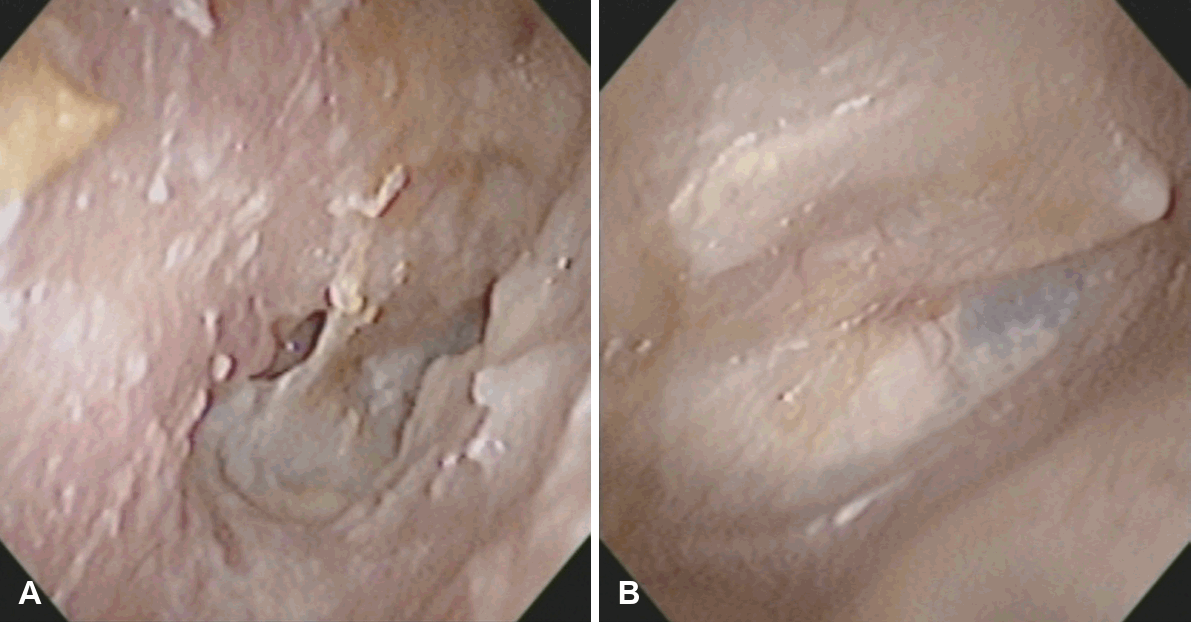

단독 외이도성형술은 기존의 외이도성형술의 적응증을 확장하여, 만성 중이나 유양돌기 수술적 치료가 필요 없는 반복성 이루 환자에서 효과적으로 이루 조절을 달성할 수 있는 유용한 술식이다(Fig. 3). 본 술식의 가장 큰 장점은 시술의 간단성과 안전성이다. 국소마취하 외래 시술로 시행 가능하며, 수술 시간이 짧고 술후 회복이 빨라 환자 부담이 적다. 또한 귀 뒤나 측두부에 외부 절개를 가하지 않고 기존 외이도 경로를 통해 접근하므로 미용상의 문제도 최소화된다. 시술 과정에서 절제 범위가 제한적이고 정상 구조를 최대한 보존하기 때문에 합병증 발생률 역시 매우 낮다.

Clinical outcome after meatoplasty (left ear). A patient with persistent otorrhea despite repeated conservative treatment (A) showed a clean, dry external auditory canal after meatoplasty (B).

단독 외이도성형술이 모든 이루 환자에게 적용되는 것은 아니다. 고막 천공이 크거나 만성 감염, 진주종 등 중이 병변이 동반된 경우에는 고실성형술이나 유양돌기절제술과 같은 근본적 치료가 우선되어야 한다. 그러나 이런 환자에서도 수술 전 외이도 입구가 좁아 이루 배출이 어려운 경우, 중이 수술과 외이도성형술을 병행해 수술 직후 건조 유지와 환기 기능을 향상시킬 수 있다(Fig. 4).

Clinical outcome of meatoplasty performed in conjunction with middle-ear surgery (right ear). A patient with chronic otitis media and refractory otorrhea despite conservative treatment (A) underwent simultaneous tympanoplasty and meatoplasty, resulting in a dry, clean canal and well-healed tympanic membrane (B).